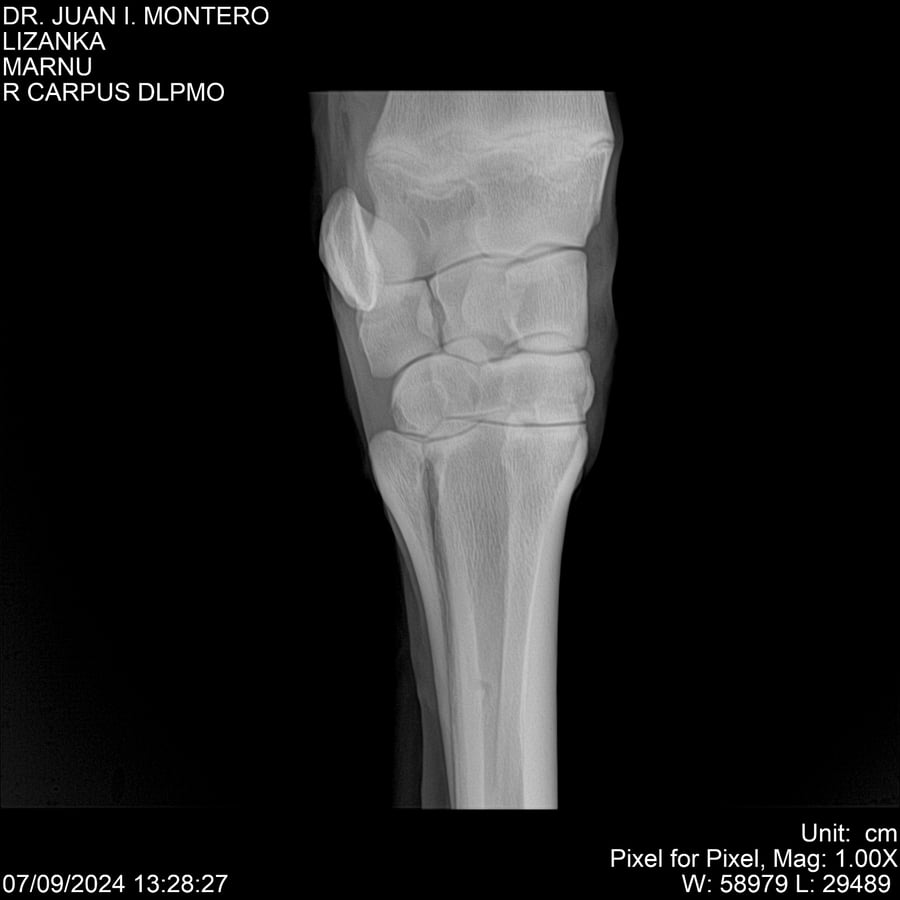

LOTE 18, LIZANKA Lote Anterior Volver al remate Lote Siguiente Ficha Contacto Montevideo - Ficha del Lote Identificador: #282512 Categoría: Yeguarizos Montevideo - 62 Visualizaciones ClicData Contacto Empresa: Abelenda N. R., Walter Hugo Nombre*: Teléfono* : E-mail* : Mensaje Enviar Registrese gratis Este contenido Exclusivo está disponible sólo para usuarios registrados Ingresar